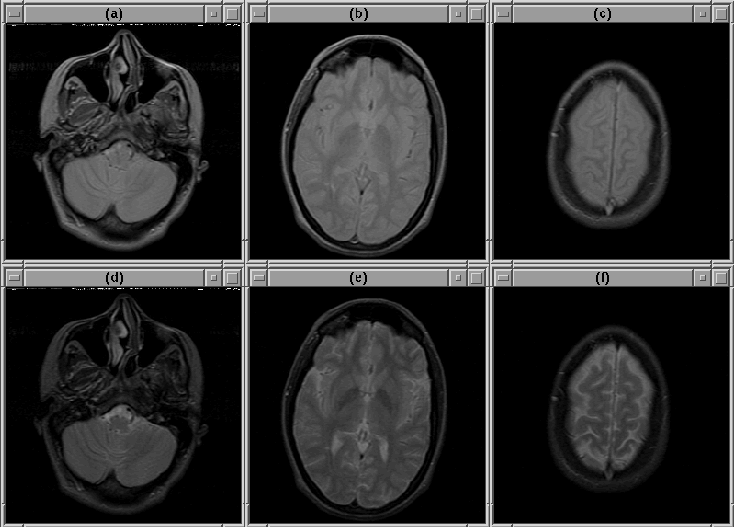

Selected slices for Data Set 2 are shown in Figure 8.2. Selected slices for Data Set 3 are shown in Figure 8.3. Notice that there is a region of bright voxels in slice 9, just above the brain, that might affect the detection of the intracranial boundary.

Figure 8.3: Selected slices from MRI Data Set 3. (Top) PD-weighted. (Bottom) T2-weighted. (a), (d) Slice 1. (b), (e) Slice 9. (c), (f) Slice 22.